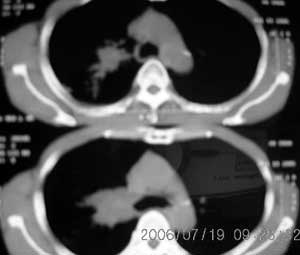

以下是引用卜一在2006-7-20 14:13:00的发言:[br]图象质量差了些,首先考虑:中心性肺癌伴阻塞性肺炎.因发生在右肺上叶尖后段,而且外带见二个空洞影,次考虑:不排除肺结核

以下是引用1983在2006-7-20 21:53:00的发言:[br]右侧中央型肺癌伴阻塞性肺炎.

以下是引用jiangjing在2006-7-20 19:22:00的发言:[br]右侧肺门见有软组织肿块,边缘不规则,不光整,其周围肺内见炎性片状影,胸片示水平裂呈弧形上移,右上叶支气管狭窄,考虑右肺中央型肺癌伴阻塞性肺炎部分肺不张。